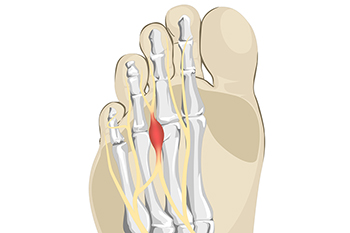

Morton's neuroma is a painful foot condition that commonly affects the areas between the second and third or third and fourth toe, although other areas of the foot are also susceptible. Morton’s neuroma is caused by an inflamed nerve in the foot that is being squeezed and aggravated by surrounding bones.

Morton's Neuroma, also called Intermetatarsal Neuroma or Plantar Neuroma, is a condition that affects the nerves of the feet, usually the area between the third and fourth toe. Neuroma refers to a benign growth that can occur in different parts of the body. Morton's Neuroma strictly affects the feet. This condition causes the tissue around the nerves that lead to the toes becoming thick, causing pain in the ball of the foot.